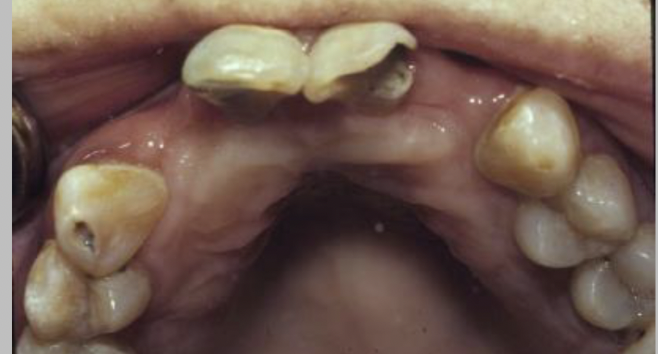

How would you describe this image?

A

slight demineralization